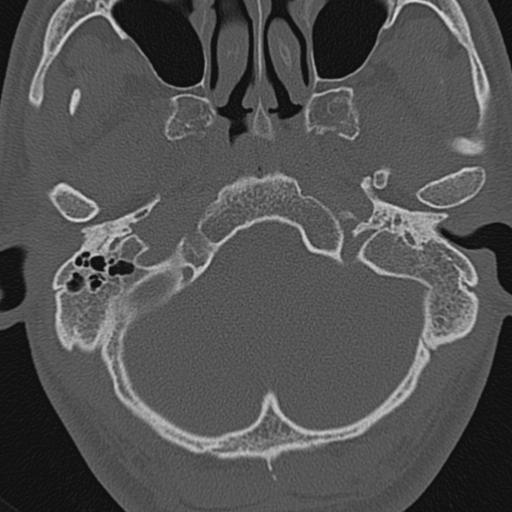

以下是引用zxl51642在2009-8-25 13:37:00的发言:[br]1、左侧慢性硬化型中耳乳突炎(中耳鼓室腔及听小骨受累),并胆脂瘤形成;2、左侧外耳道软组织密度影填塞,考虑炎性肉芽肿,建议结合临床;3、右侧颈静脉窝较左侧明显扩大,不排除颈静脉球瘤,建议mr进一步检查。

以下是引用随光逐影在2009-8-25 19:05:00的发言:[br]1)左侧慢性中耳乳突炎(肉芽肿或胆脂瘤形成),左侧外耳道炎性肉芽肿。2)右侧颈静脉球高位。